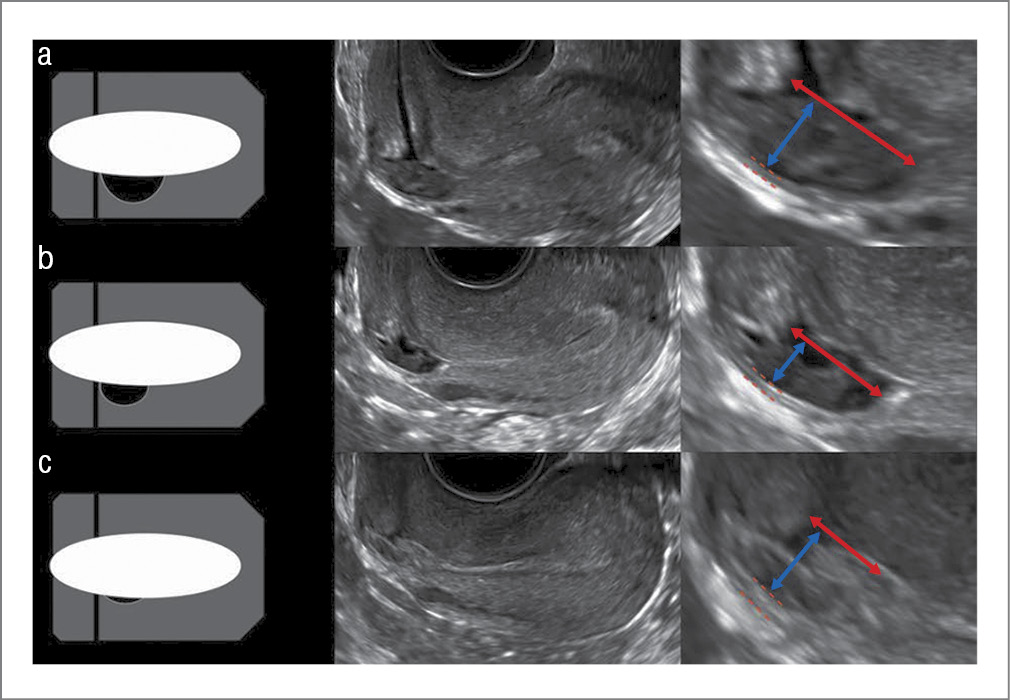

Важно отметить, что длина и глубина ниши, а также толщина остаточного миометрия могут значительно изменяться на протяжении МЦ. Так, на схематичных изображениях и ТВУЗИ матки в сагиттальной плоскости продемонстрировано изменение размера и объема маточной ниши в разные фазы МЦ у одной и той же женщины (рис. 5) [41].

Рис. 5. Динамика изменения толщины остаточного миометрия на протяжении МЦ: а – менструация; b – фолликулярная фаза; c – лютеиновая фаза [41].

Fig. 5. Change over time of the residual myometrium thickness during the menstrual cycle: a – menstruation; b – follicular phase; c – luteal phase [41].